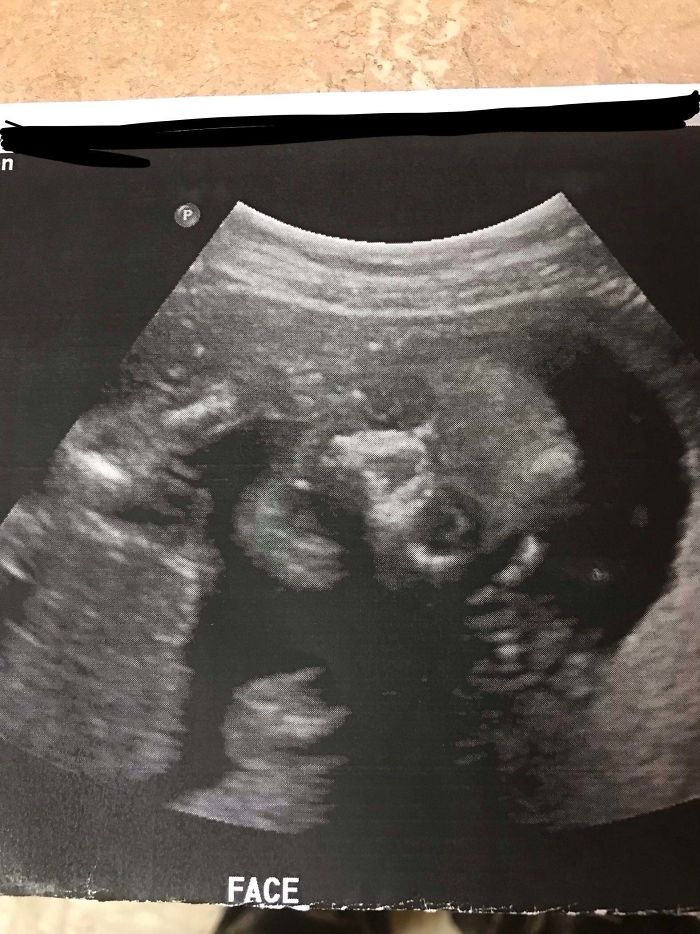

Anoche estaba seguro de que había un bebé fantasma en la cuna con mi hijo